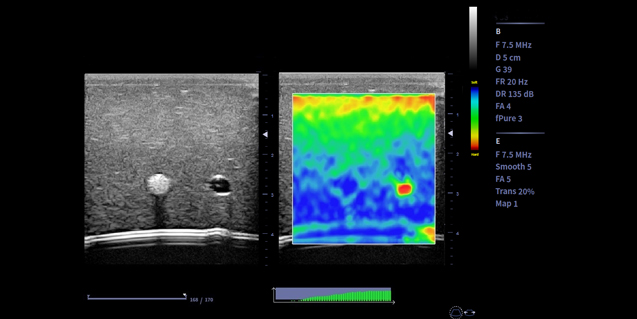

微血流技术 Micro Flow

- 微血流成像技术基于时间,空间和参数信息共同检测血流,可提高对低速血流的灵敏度,有效抑制非血流信号的干扰

-

临床图像